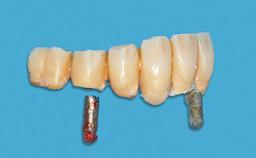

An 83-year-old man presented together with his caregiver at the dental department of the Medical University of Innsbruck, Austria with complaints of swelling in the right maxillary canine area and loss of retention of his 5-years-old mandibular denture. The patient had a significant medical history (20 years) of bipolar affective disorder with moderate depression (F 31.3) and dementia in Alzheimer’s disease (F 00.2). The patient had been in ambulant psychiatric therapy for his depressive illness for the past 20 years. He lived alone and had no children; his sister assisted with daily living. She reported that the patient exhibited compulsive hoarding behavior. In the previous two months, she had noted increasing disorientation and vertigo in the patient. She therefore accompanied him for a medical consultation at the Department of Psychiatry and Psychotherapy of the Medical University of Innsbruck. He was released home after a 6-week inpatient stay.

# of Implants 2

Type of Implants One-Piece

Attachment One-Piece

Prosthesis Type RDP

Defining Characteristics Fully edentulous lower jaw to be rehabilitated with an implant-borne removable overdenture